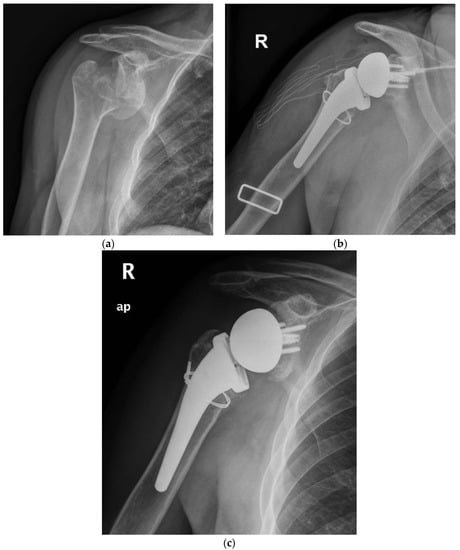

In the period analyzed, a comprehensive 88 cases of acute proximal humerus fractures were managed with a RTSA with a cementless and metaphyseal stem fixation in our institution. By applying the inclusion and exclusion criteria, 21 cases were finally selected for group A and 67 for group B. Two patients (9.5%) for group A and 16 (23.8%) for group B were excluded, being lost to the follow-up or for inadequate radiographic examination. Similarly, one patient for each group and one patient for group B were surgically revisited for periprosthetic fracture after a fall and a deep infection, respectively. The selection led finally to a group A of 18 patients (Figure 1 and Figure 2) and a group B of 50 patients.

Figure 1.

(a) Preoperative radiographic image of right shoulder showing acute (Neer three-part) proximal humeral fracture with calcar involvement. (b) Immediate postoperative film of right shoulder showing calcar fragment fixation with steel wire cerclage. (c) 5.7 years postoperative film of right shoulder showing stem subsidence and healing of tuberosity and medial calcar.

(a) Preoperative radiographic image of right shoulder showing acute (Neer four-part) proximal humeral fracture with calcar fragment. (b) Immediate postoperative film of right shoulder showing calcar fragment fixation with steel wire cerclage. (c) 5.5 years postoperative film of right shoulder showing healed tuberosity and medial calcar.

The overall complication rate at the final follow-up was 28% (19 patients, Table 3). Postoperative complications included tuberosity non-union in ten patients, scapular notching in two patients, radiolucent lines in two patients (one in group A and one in group B), subsidence in three patients (one for group A, 5.5% and two for group B, 4%), heterotopic ossification in one patient and superficial infection in one patient. The subsidence observed (Figure 1c) was never associated with any symptoms, pain, or evident implant loosening throughout the follow-up. Bone healing of the medial calcar fragment was always observed with heterotopic ossifications in two patients.

The experience of cementless fixation thus far published has regarded mainly three-, four-, and rarely two-parts PHFs. No mention may be found on more severe fracture patterns, such as those with a medial calcar fragment [23]. Moreover, most of the series have employed standard or long stems with a press-fit achieved often in the diaphyseal bone. Our series supports the safety and viability of RTSA with a cementless and metaphyseal stem’s fixation for two-, three-, and four-part PHFs but as well in selected fractures with a calcar fragment that is sizable to be fixed with steel wire cerclage (Figure 1 and Figure 2). At a minimum follow-up of five years, the clinical outcomes (ASES score of 89.2, Simple Shoulder Test score 91.1 and NRS pain of 0.8) were satisfactory and supported by the comparison with a control group of patients without the calcar fragment (ASES score of 91.6, Simple Shoulder Test score 90.4 and NRS pain of 0.5). For both groups, the results are likewise comparable to those achieved by other series with either cementless or cemented stems.